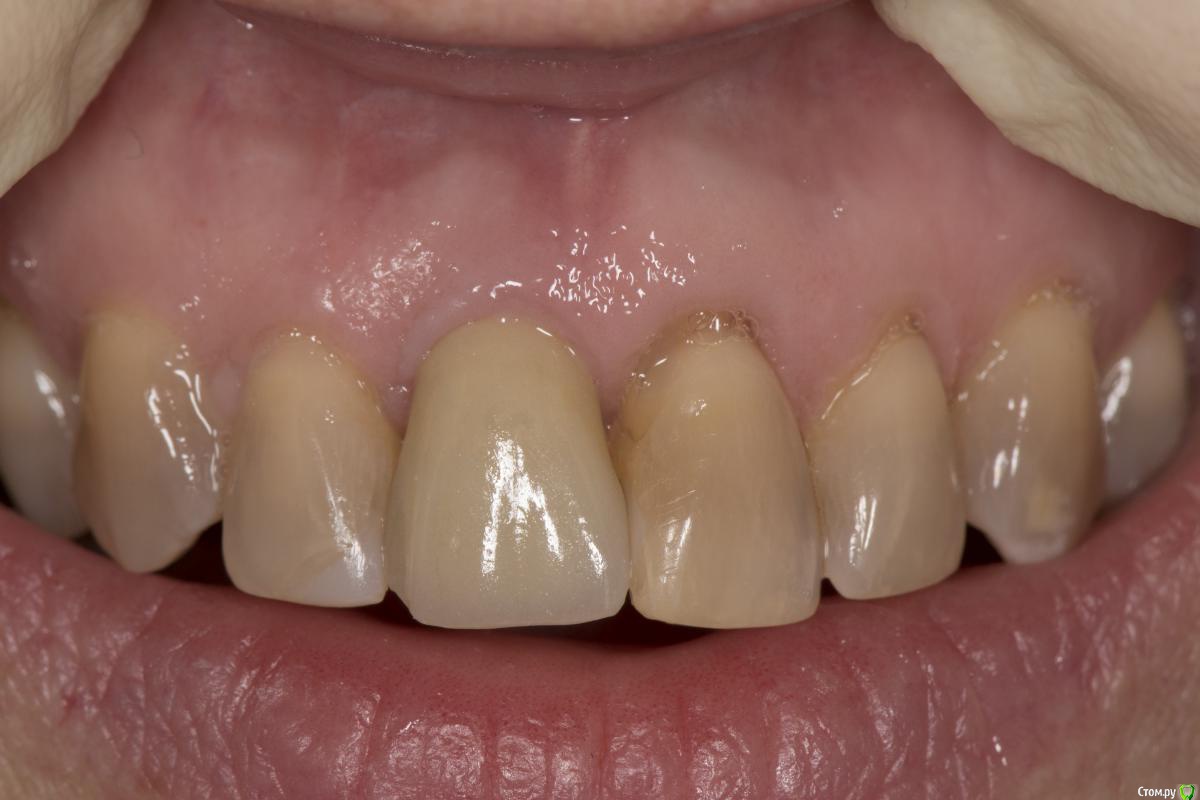

K.E. Опубликовано 27 февраля, 2016 Автор Поделиться Опубликовано 27 февраля, 2016 Ситуация на данный момент. Снимок рентгена сделан с экрана монитора. 5 Ссылка на комментарий